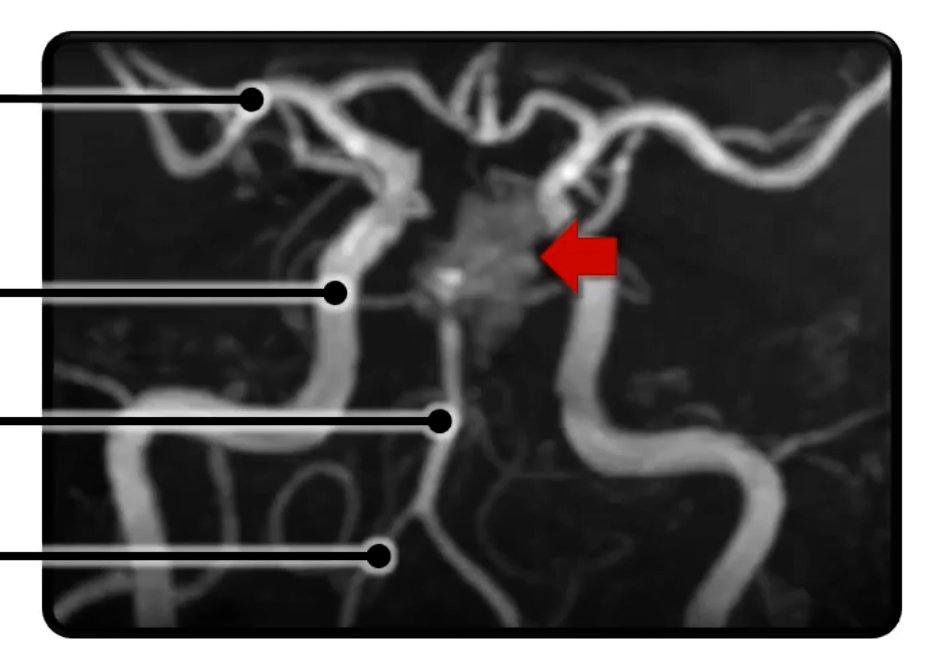

What is the pathology in this radiograph?

ruptured aneurysm

What are the arteries in this radiograph? (from top to bottom)

Middle Cerebral Artery

Internal Carotid Artery

Basilar Artery

Vertebral Artery